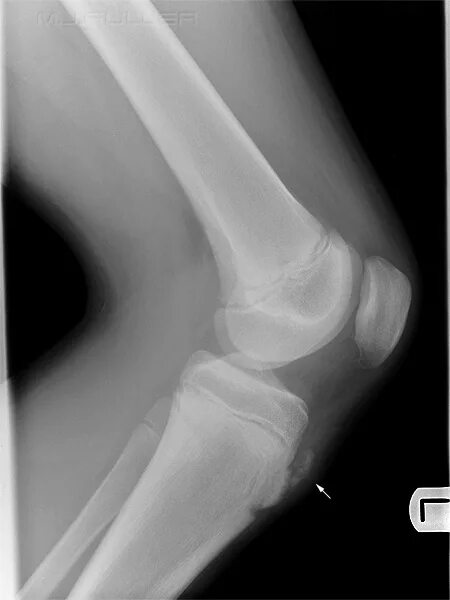

Болезнь шляттера код по мкб